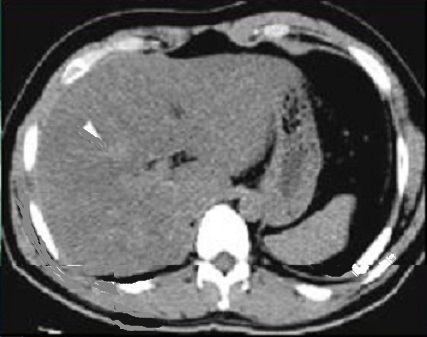

On peu gradation steatose du foie sur TDM :

| |

Grade 1 : Les vaisseaux sont visibles en

peripherique 1/3 externe du foie |

Grade 2 : Les vaisseaux sont visibles seulement

jusqu'au 1/3 moyen du foie |

Grade 3 : Les vaisseaux sont visibles seulement dans

le 1/3 interne du foie |

Grade 4 : Les vaisseaux ne sont plus visibles dans

1/3 interne du foie |

Grade 5 : Les vaisseaux sont en visibles positif

|

Steatose grade 1 : Les

vaisseaux sont visibles en 1/3 externe du foie |

Steatose grade 2 : Les

vaisseaux sont visible jusqu'au 1/3 moyen du foie |

Steatose grade 3 : Les

vaisseaux sont visible seulement dans le 1/3 interne

du foie |

Steatose grade 4 : Les

vaisseaux ne sont plus visibles dans 1/3 interne du

foie |

Steatose grade 5 : les

vaisseaux sont en visibles plus hyperdense que

le foie |